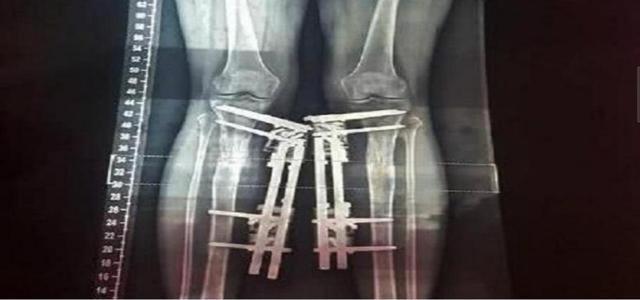

遗憾的是最终问题还是找上来了。一次她做了一个腿部的整容手术,抱着极大的信心她再一次的进入了整容的手术室,这次出现问题了。原因是整容医生在做手术时不小心把钢针打歪了,这让她的腿严重变形,而且已经完全走了样。